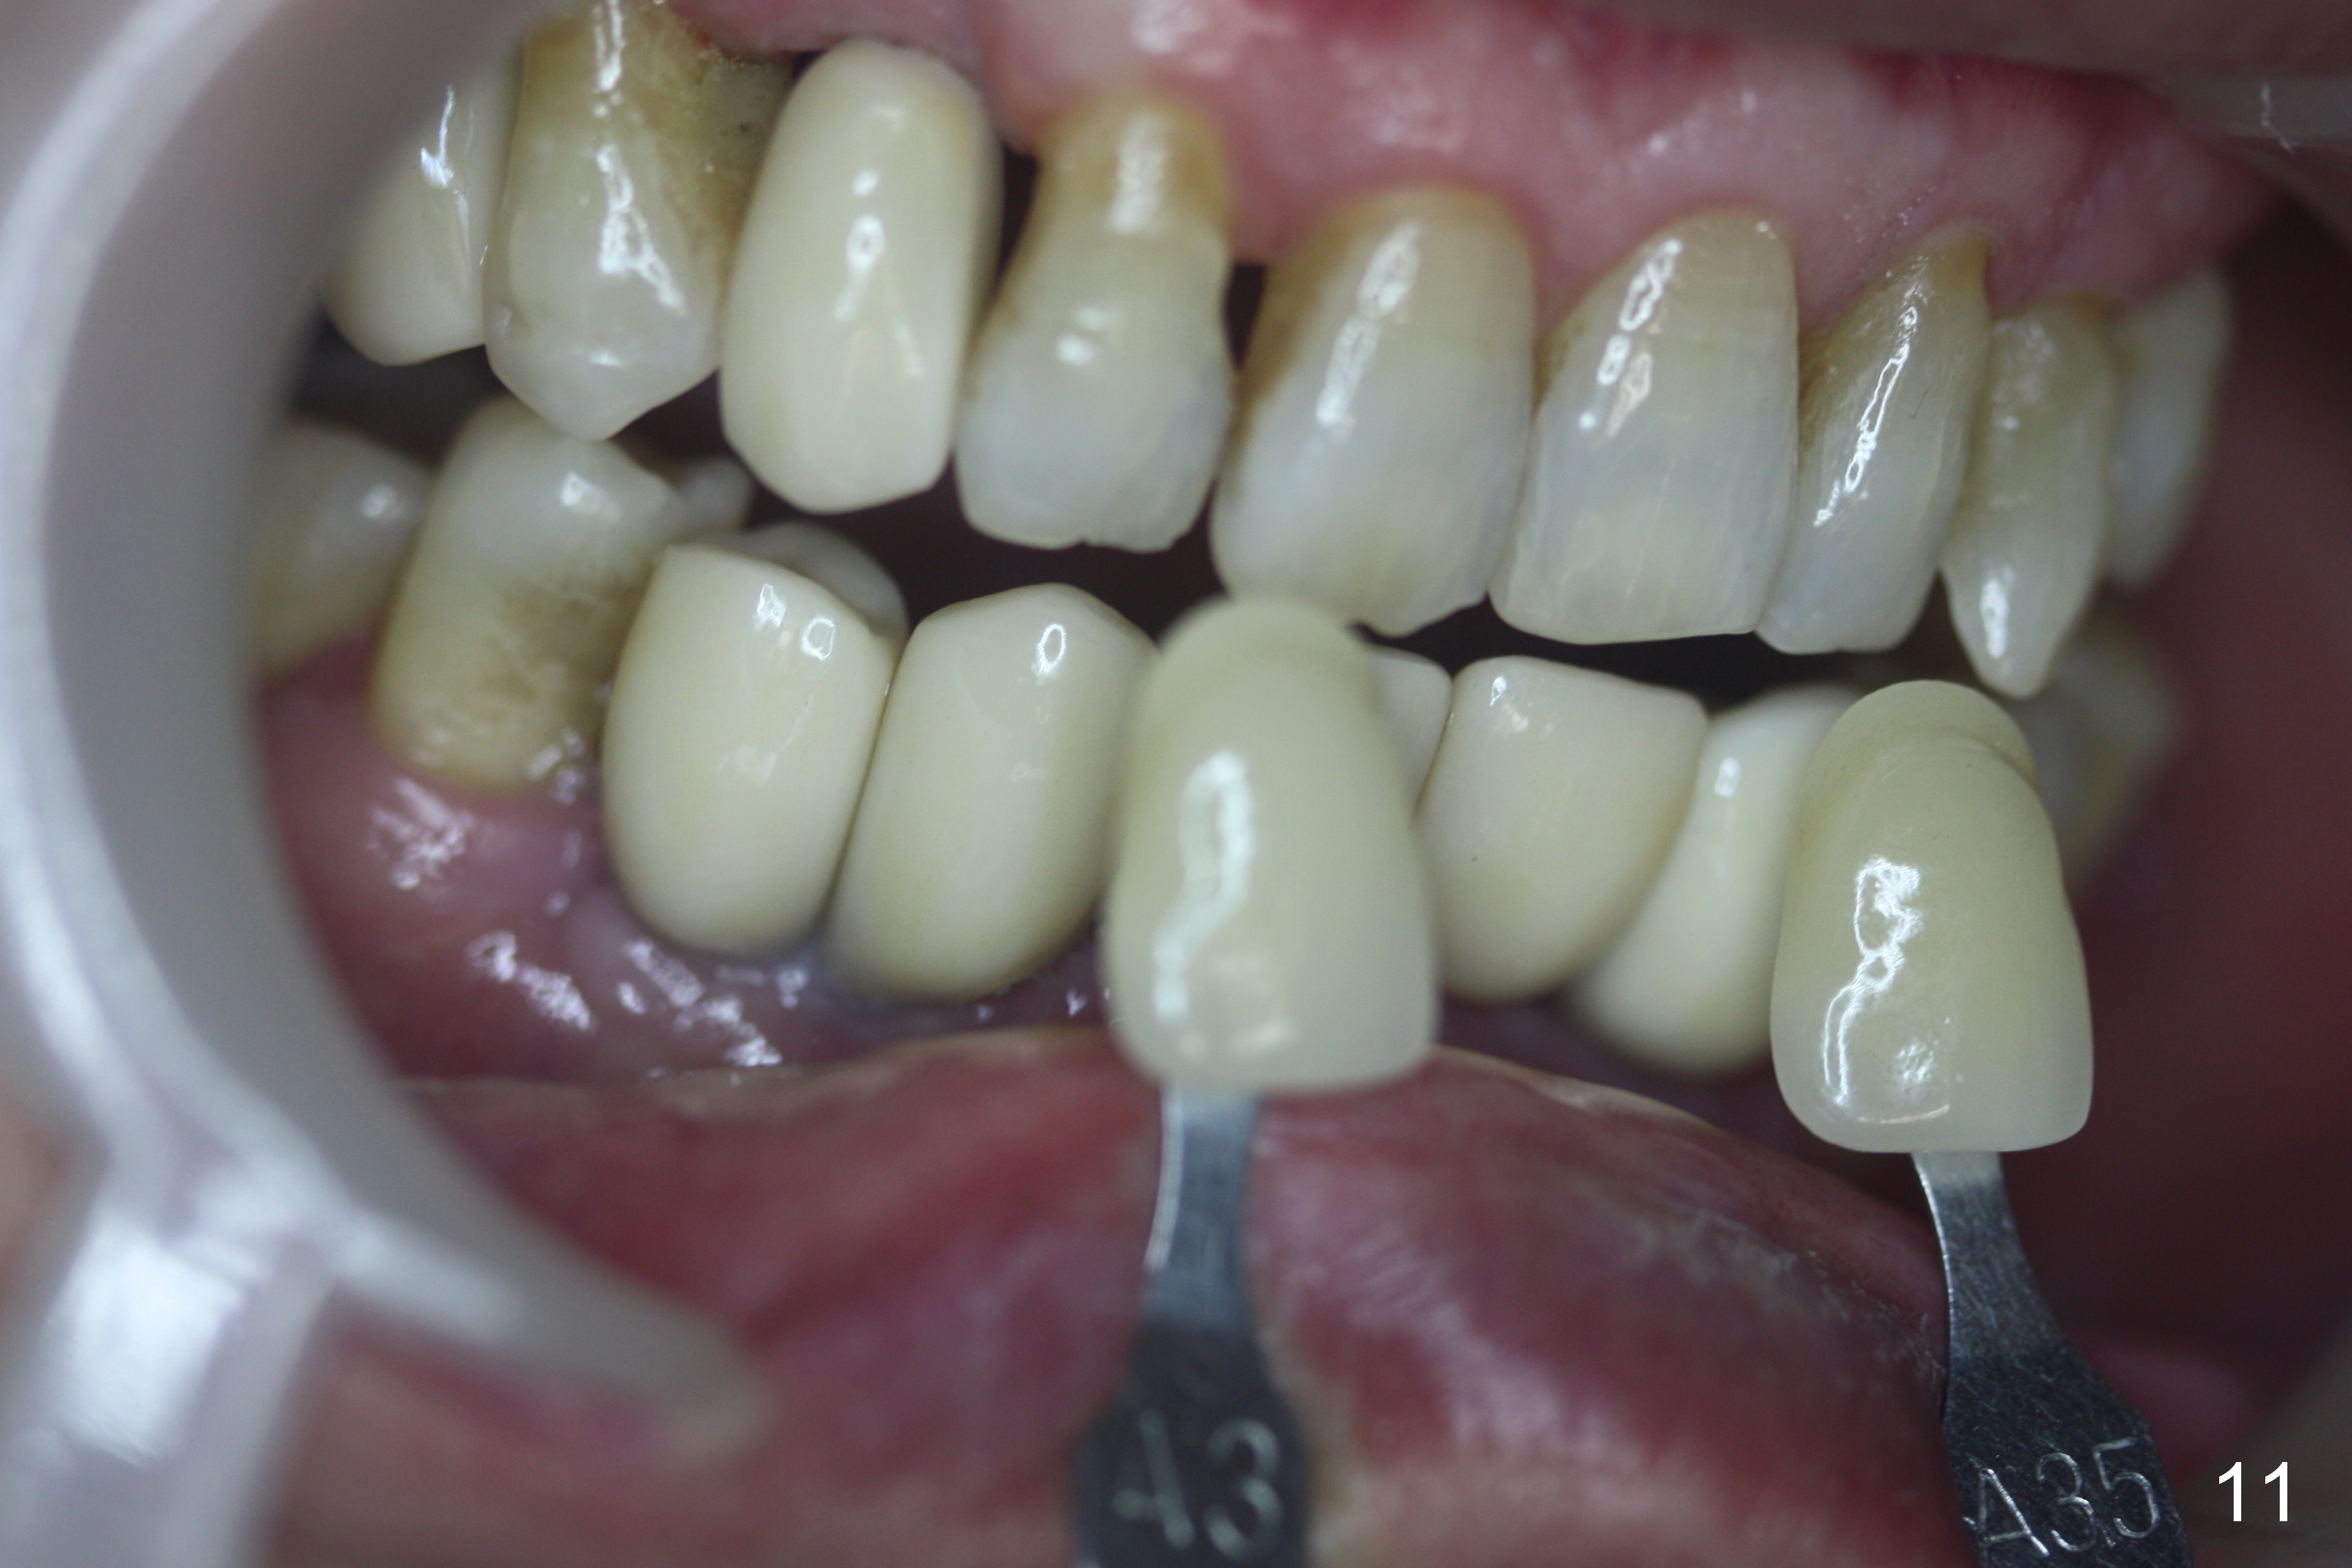

When the final crowns are seated, the shade is off. It appears that C3 is appropriate (Fig.10,11). Please make the crowns more transparent.